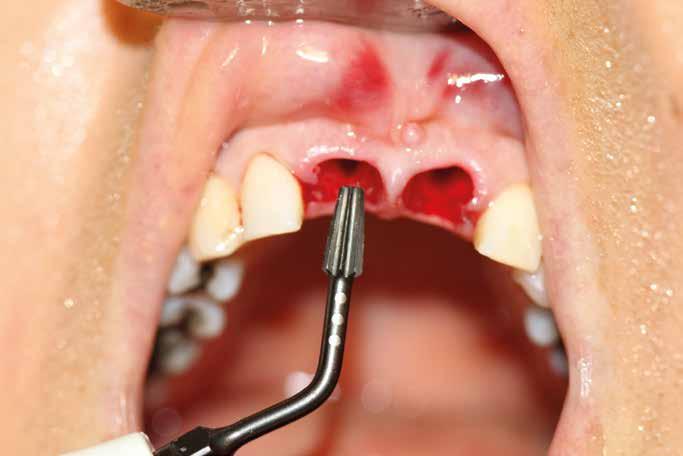

Esempio chirurgico di accesso tra 2 elementi dentari con conformazione della cresta alveolare ampia. Incisione del lembo in cre sta senza scarichi laterali con sollevamento di 2 lembi, palatale e vestibolare; si può notare come quest’ultimo non si estenda oltre

Una incisione lineare netta si estende coinvolgendo minimamente il dente mesiale e maggiormente in direzione distale, consente di evitare l’esecuzione di incisioni di scarico che provocano una interruzione della vascolarizzazione maggiore, senza ridurre la visibilità del campo operatorio.

Disegno del lembo d’accesso con spostamento della incisione crestale sul versante palatino. Lo scollamento della porzione vestibolare deve avvenire con uno scollatore di piccole dimensioni e l’ausilio di una pinza chirurgica